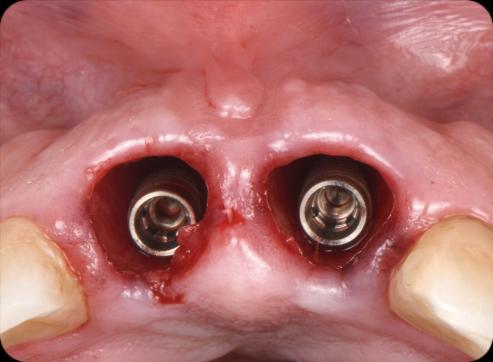

• Two BioHorizons Tapered Pro Conical implants of 3.8 x 15mm were placed according to the plan (3).

• Implants immediately after installation (4). 1

• Implants immediately after installation (1).